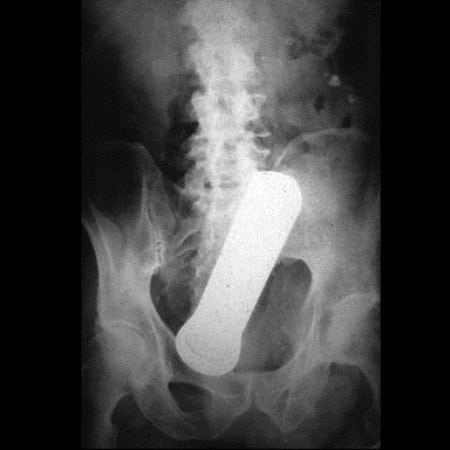

4. Φακός